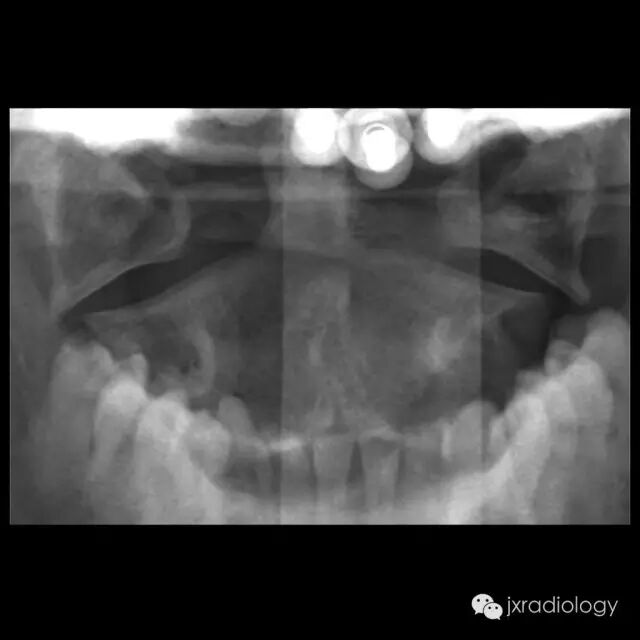

寰椎骨折又名Jefferson骨折(因由Jefferson于1920年首次报道,故此命名)。环形的寰椎遭受轴向压缩和头部向后、下转伸时,暴力经枕骨髁作用于寰椎侧块,并引起寰椎骨环爆裂(散)骨折。寰椎的前弓与后弓双侧骨折,以致侧块被挤压而向四周分离

主要介绍颈椎开口位的X线平片表现:开口位可发现寰椎左右增宽,且与齿突的距离双侧常呈不对称状。如双侧侧方移位总和超过7mm者,则表示寰椎横韧带断裂、寰椎骨折。

正位与齿状突对比似双侧开门样增宽,为此加深记忆,故得此名,如有不妥,敬请谅解(小编)。